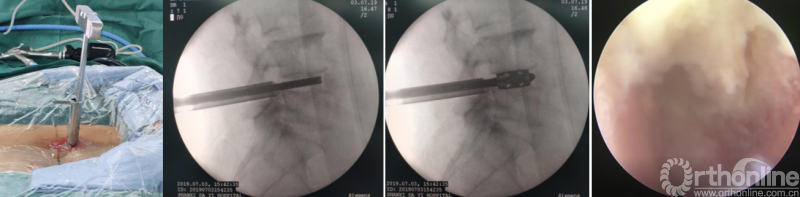

PE-PLIF技术十步法

详细步骤:一定、二辨、三凿、四分、五咬、六切、七旋、八铰、九填、十置

第一步“定”:X线定位在上位椎体下关节突下三分之一部;

第二步“辨”:镜下辨别下关节突关节囊;

第三步“凿”:凿除部分下关节突,显露上关节突及黄韧带;

第四步“分”:分离上关节突及黄韧带;

第五步“咬”:咬除部分上关节突,显露椎间盘及神经根;

第六步“切”:切除椎间盘;

第七步“旋”:旋转舌形套管保护神经根;

第八步“铰”:盲视下可撑开铰刀置入,撑开并处理上下终板;

第九步“填”;椎间隙填塞植骨;

第十步“置”:置入融合器、经皮钉。